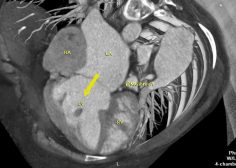

Criss-cross heart

Mohamed Gibreel , FEBR (Fellowship of Egyptian Board of Radiology ) Cardiac imaging consultant at Aswan heart center -Magdi Yacoub Foundation , Egypt